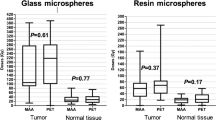

Patients with grade 2 or higher change in post-treatment albumin (74.1 vs. 43.3 Gy, p = 0.013), bilirubin (84.2 vs. 43.8 Gy, p < 0.001), and AST (94.5 vs. 47.1 Gy, p = 0.048) received higher non-tumoral liver doses compared to patients without laboratory toxicity (Fig. 2). Non-tumoral liver dose was not statistically higher for patients that exhibited grade 2 or higher change in ALT or leukopenia. Median non-tumoral liver doses for the composite and individual toxicities are shown in Table 3.